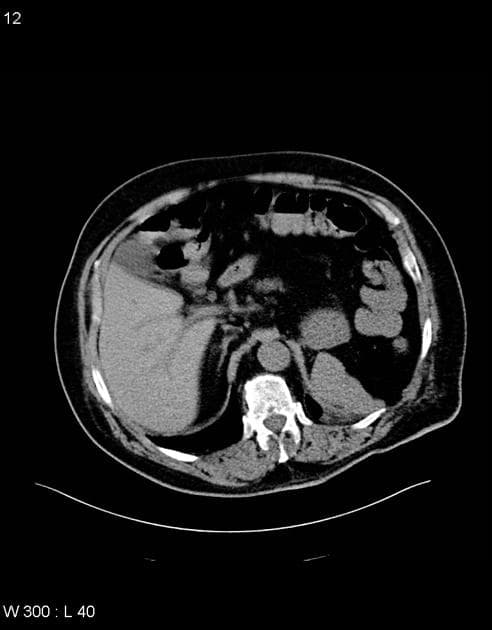

Khối đặc ở cực dưới thận trái, nằm ở vùng vỏ thận, nghi ngờ cao là khối u (high suspicion of tumor).

Các nang đơn giản ở thận.

Nhiều nang thận hai bên.

Nhiều nang nhỏ ở tụy.

Khối bắt thuốc ở cực dưới thận trái.

U tế bào ống thận (Renal cell carcinoma - RCC) có thể xuất hiện ở đến 40% trường hợp và là một trong những biến chứng đáng lo ngại nhất. RCC ở bệnh nhân vHL thường xuất hiện ở độ tuổi sớm hơn, như trong trường hợp này là bệnh nhân ở độ tuổi 20.

Tổn thương thận đã được xác nhận là u tế bào ống thận dạng nang (cystic renal cell carcinoma) qua sinh thiết định hướng CT.

- "Ung thư biểu mô tế bào thận (RCC) xảy ra ở khoảng 40% bệnh nhân VHL và thường khởi phát ở độ tuổi trẻ hơn."